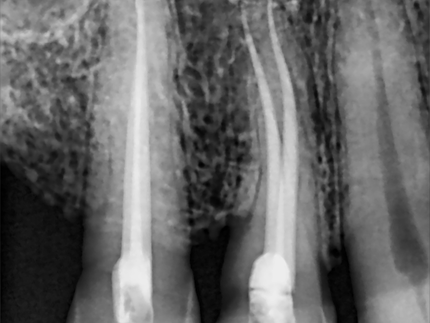

Endodontic treatment aims to repair and save a badly damaged infected tooth. the procedure involves removing the damaged pulp or nerve, cleaning disinfecting it, and then filling and sealing it.

The following cases were done using MTWO rotary endodontic instruments by VDW for fast and safe root canal preparation.